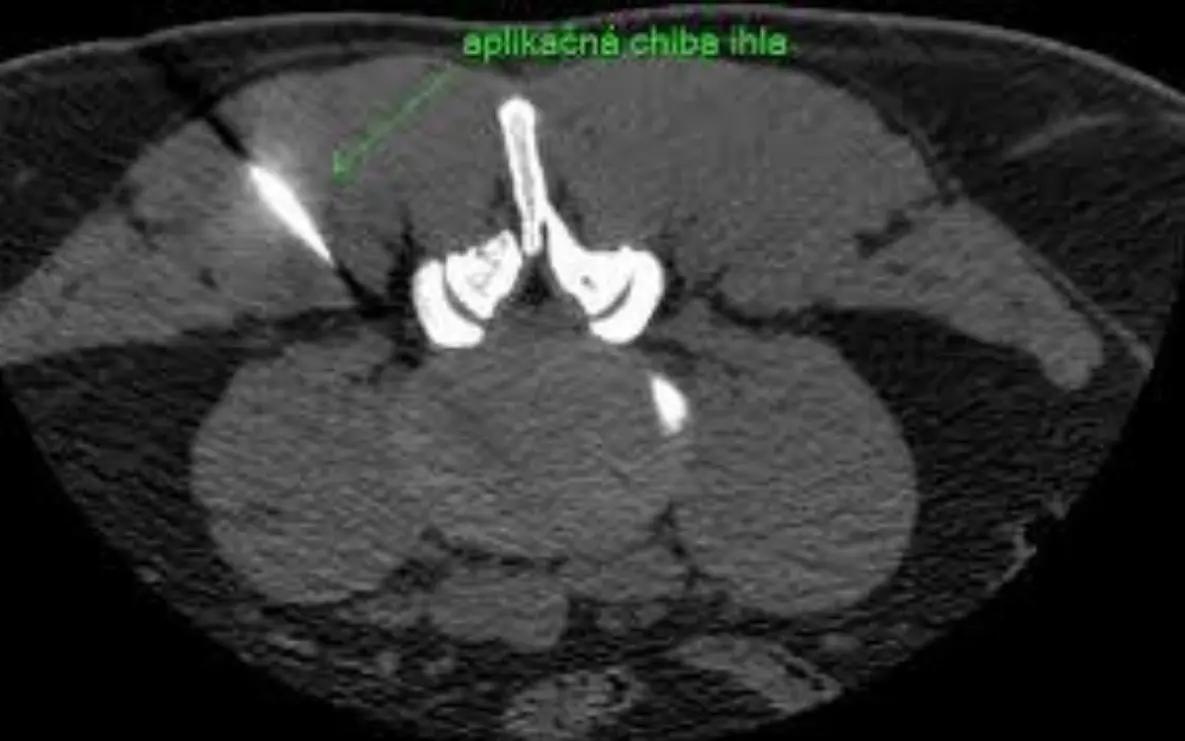

Aplikácia ihly pod CT

Výkon prebieha pod CT prístrojom, pacient leží v polohe na bruchu. Celý proces je rýchly a dobre znášaný.

1 Určenie miesta vpichu pomocou CT scanov, dezinfekcia a zavedenie Chiba ihly.

2 Kontrola polohy ihly CT scanmi až k cieľovému koreňu/kĺbu.